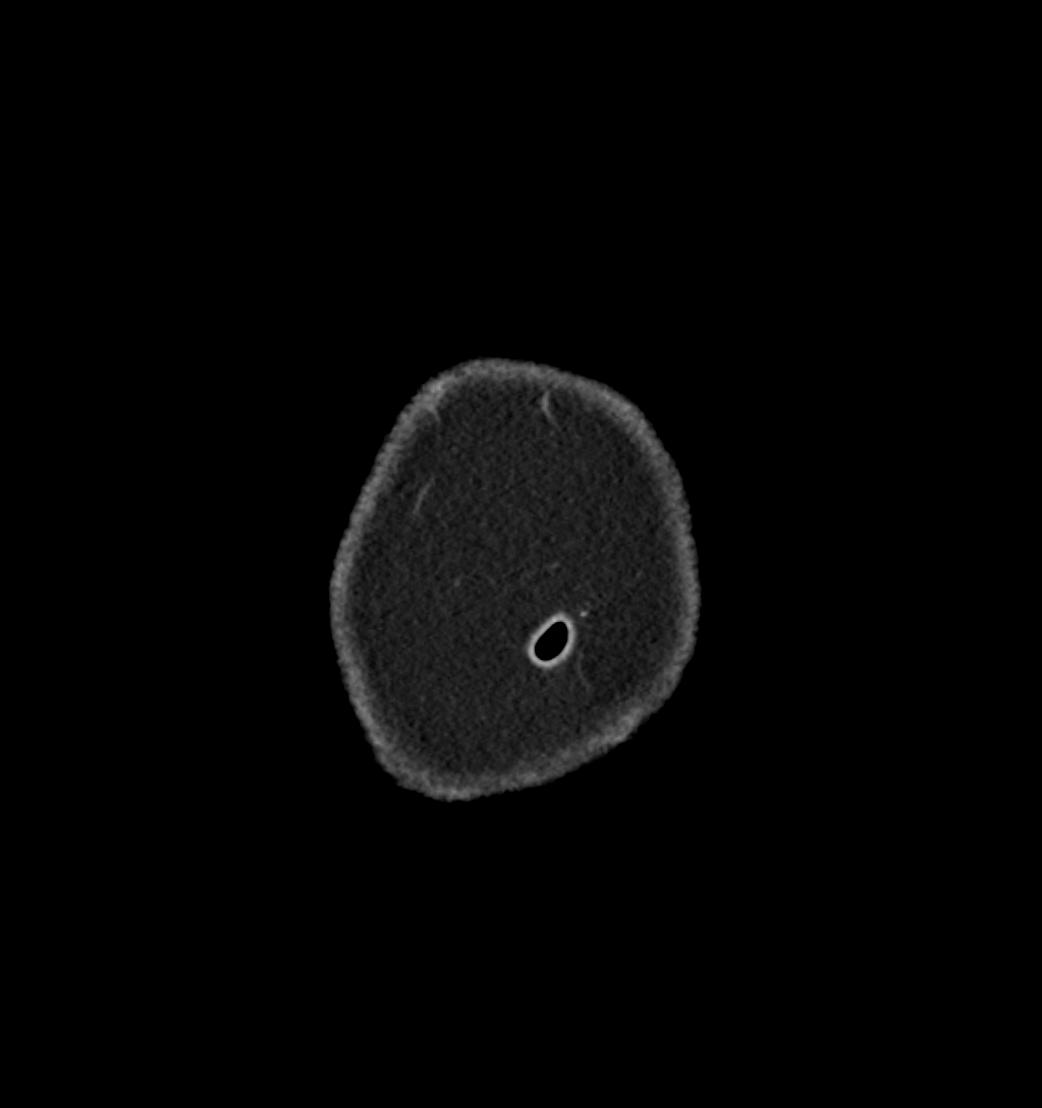

Patient: Padmakumar A. , *1988-04-24, PID: 3000069741773230809

Study Description: CT ABDOMEN

Image Series: Abdomen Cor 3mm [4]

<< Previous | Image 5 of 119 | Next >>